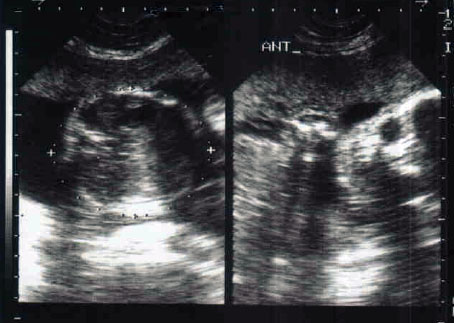

Attachment 3129